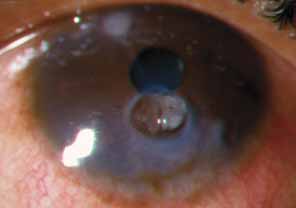

The current number of procedures performed on an annual basis is decreasing slightly; a total of 32,744 corneal transplants were performed in 2002, marking the first time since 1986 that the number of procedures performed has been less than 33,000.1 This downward trend has coincided with the decrease in incidence of pseudophakic corneal edema (PCE) (Fig. 1) and aphakic corneal edema (ACE). The percentage of PKs performed to treat PCE has dropped from 19.8% in 2001 to 18.4% in 2002, which was the lowest percent reported in this category in 15 total years of tracking by the Eye Bank Association of America (EBAA). It is possible that this decrease reflects improved cataract removal technique and technology, such as phacoemulsification and posterior chamber intraocular lens placement. The indications for PK have shifted over the past several decades, with PCE the most common indication since 1980, whereas keratoconus (Fig. 2) and ACE were the most common indications prior to 1980.2 Data is tracked for a total of 16 indications for transplant by the EBAA. Pseudophakic corneal edema, keratoconus (particularly in younger patients), Fuchs' endothelial dystrophy (particularly in older patients), and regrafting secondary to rejection or other reasons currently sit atop the list of indications for PK.

Fig. 2 Keratoconus is one of the most common indications for penetrating keratoplasty. Descemet's tears may occur spontaneously in this condition, leading to acute hydrops.